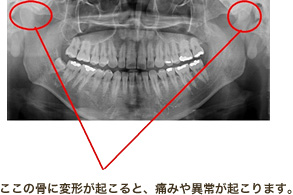

アゴの構造

顎の関節や筋肉に痛みや違和感が出る病気です。

主な症状は顎の痛み・口の開閉時の音・口が開けにくいなどです。